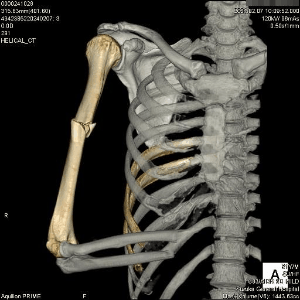

今年の初め頃、通勤途中に車に跳ねられまして、右上腕骨折の重傷を負ってしまいました。何とも痛々しいバキ折れ方をしております。ホントに痛かった(TT)

手術の結果、改造人間になってしまった私。